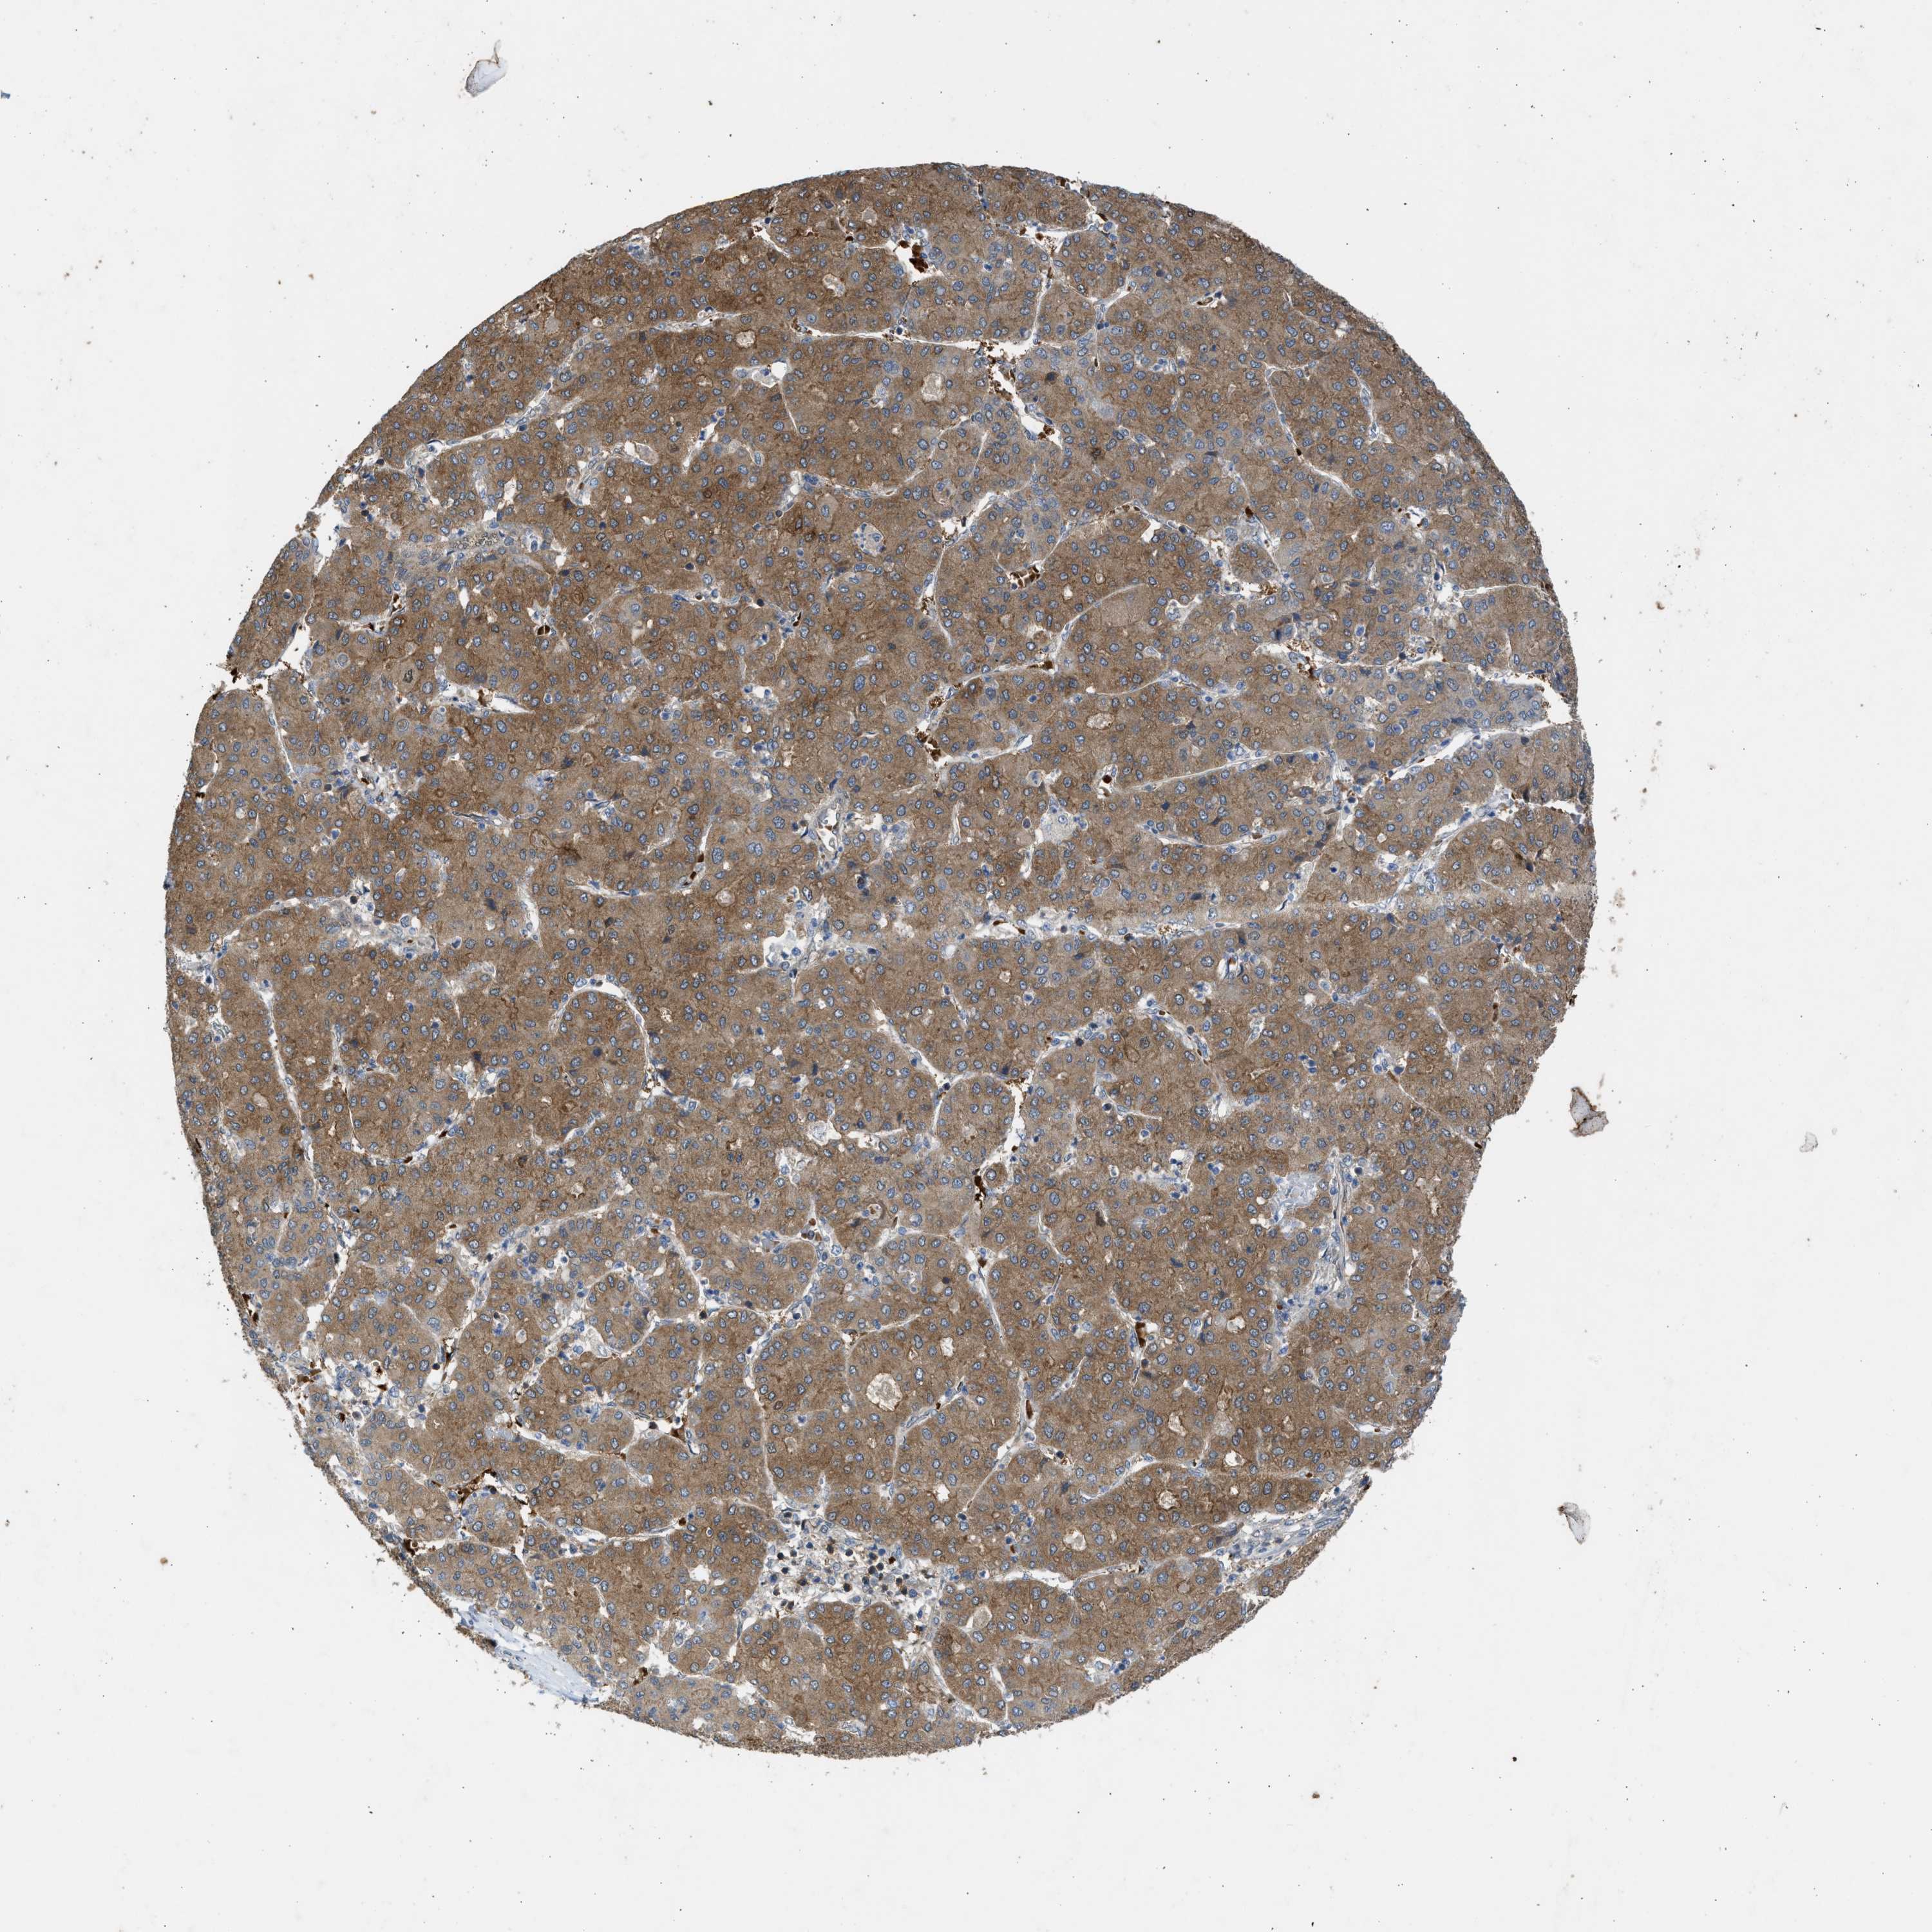

LIVER CANCER - Protein expressioni

A mouse-over function shows sample information and annotation data. Click on an image to view it in a full screen mode. Samples can be filtered based on level of antibody staining by selecting one or several of the following categories: high, medium, low and not detected. The assay and annotation is described here.

Note that samples used for immunohistochemistry by the Human Protein Atlas do not correspond to samples in the TCGA dataset.

Antibody stainingi

Antibody staining in the annotated cell types in the current human tissue is reported as not detected, low, medium, or high, based on conventional immunohistochemistry profiling in selected tissues. This score is based on the combination of the staining intensity and fraction of stained cells.

Each image is clickable and will lead to virtual microscopy that enables deeper exploration of all samples and also displays staining intensity scores, fraction scores and subcellular localization as well as patient and tissue information for each sample.

Antibody CAB018561

Staining

High

Medium

Low

Not detected

Intensity

Strong

Moderate

Weak

Negative

Quantity

>75%

75%-25%

<25%

None

Location

Nuclear

Cytoplasmic/membranous

Cytoplasmic/membranous,nuclear

Cholangiocarcinoma

Carcinoma, Hepatocellular, NOS